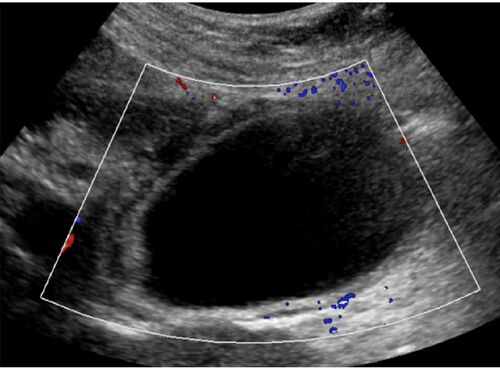

case133:嘔吐と右上腹部痛で受診した77歳女性(Int J Surg Case Rep. 2021 Mar;80:105614.)

病歴/身体所見 ・77歳女性 ・前日より複数回の嘔吐と右上腹部痛を発症してER受診 ・過去数か月にわたって、持続時間10-15分ほどの自然寛解する同様の疼痛を自覚していた ・既往歴は特になく、内服薬もなし 検査所見 ・血液検査…白血球とCRPがわずかに上昇 ・…